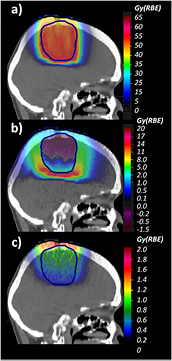

In figure 8, we illustrate the results for the head treatment plan in terms of  with the full calculations in panel (a) and the difference in terms of

with the full calculations in panel (a) and the difference in terms of  between full calculations and the approximation of a constant RBE of 1.1 in panel (b). In panel (c), the

between full calculations and the approximation of a constant RBE of 1.1 in panel (b). In panel (c), the  differences between the results shown in (a) and those obtained by weighting only the biological effect of Z = 1 particles are plotted.

differences between the results shown in (a) and those obtained by weighting only the biological effect of Z = 1 particles are plotted.

Figure 8. a) MC-calculated  distribution applying the introduced RBE models for both Z = 1 and Z = 2 particles for the head case. (b) Differences between MC-calculated

distribution applying the introduced RBE models for both Z = 1 and Z = 2 particles for the head case. (b) Differences between MC-calculated  displayed in (a) and that obtained using the clinical constant RBE of 1.1. (c) Differences between MC-calculated

displayed in (a) and that obtained using the clinical constant RBE of 1.1. (c) Differences between MC-calculated  displayed in (a) and applying the introduced RBE model weighting only the Z = 1 particles. The PTV is displayed with lines.

displayed in (a) and applying the introduced RBE model weighting only the Z = 1 particles. The PTV is displayed with lines.

Download figure:

Standard image High-resolution image differences up to about 20 Gy (RBE) in the distal part of the field have been found, which, however, do not correspond to any critical structure. This large difference is mainly due to the low

differences up to about 20 Gy (RBE) in the distal part of the field have been found, which, however, do not correspond to any critical structure. This large difference is mainly due to the low  value assigned to the brain and the higher LET components in this region. Negative values, corresponding to RBE values lower than 1.1, have been seen in the entrance part of the PTV due the high

value assigned to the brain and the higher LET components in this region. Negative values, corresponding to RBE values lower than 1.1, have been seen in the entrance part of the PTV due the high  value assigned. Weighting the biological effect of He secondaries increases the mean

value assigned. Weighting the biological effect of He secondaries increases the mean  in the PTV by about 0.6 Gy (RBE). Variations in the EC up to 1.4 Gy (RBE) have been found.

in the PTV by about 0.6 Gy (RBE). Variations in the EC up to 1.4 Gy (RBE) have been found.